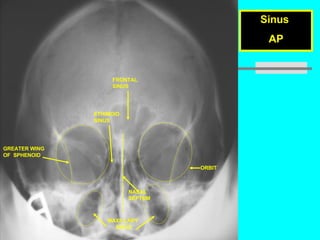

Prof. Z. Vinokur Sinus  AP FRONTAL  SINUS ETHIMOID  SINUS ORBIT NASAL SEPTUM GREATER WING  OF  SPHENOID MAXILLARY  SINUS

Prof. Z. VinokurSinus AP FRONTAL SINUS ETHIMOID SINUS ORBIT NASAL SEPTUM GREATER WING OF SPHENOID MAXILLARY SINUS